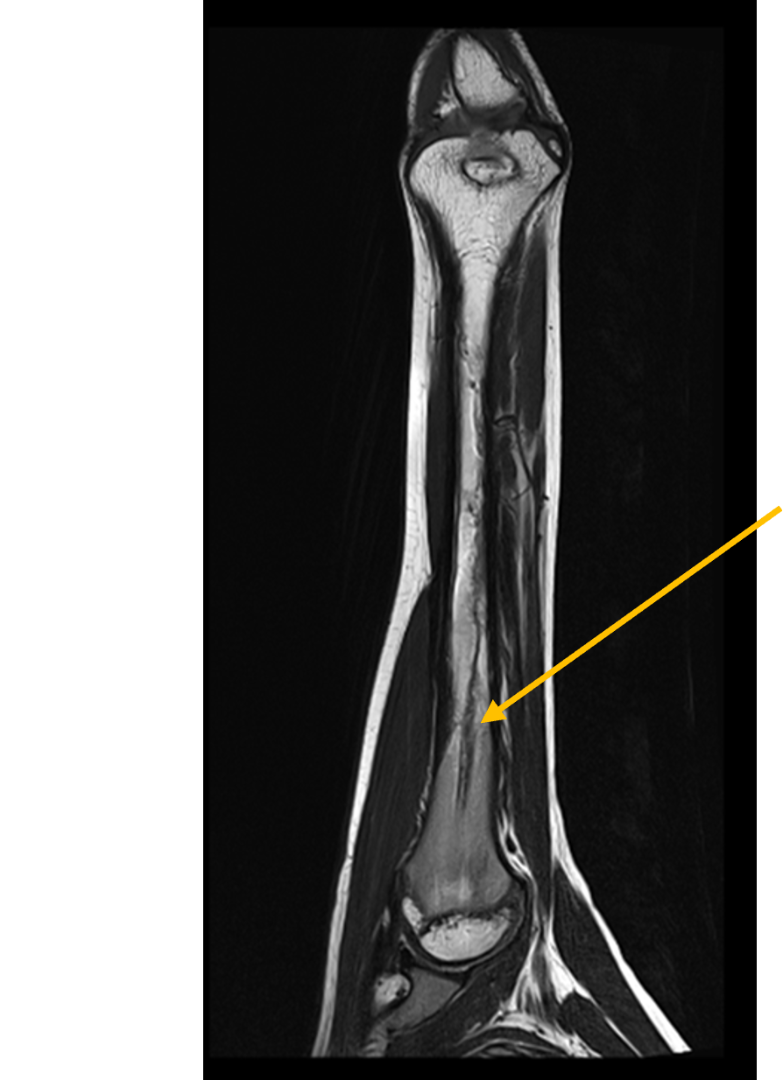

- (A,B) : MR LEFT FOREARM

- B 1 : Tract of previous intramedullary nail seen in shaft of humerus, along with mild diffuse cortical thickening.

- B 2 : Volume loss with fatty atrophy of brachioradialis, supinator, extensor carpi radialis longus and brevis muscles ,due to chronic denervation changes.